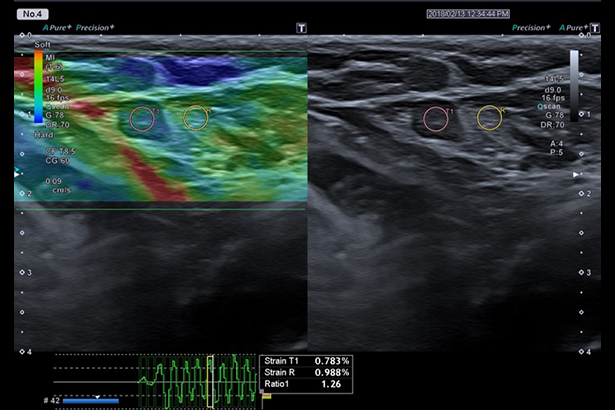

使用原始數據功能,幫助您定位并定量評估可觸及的腫物,高準確性、高敏感度、高重復性。